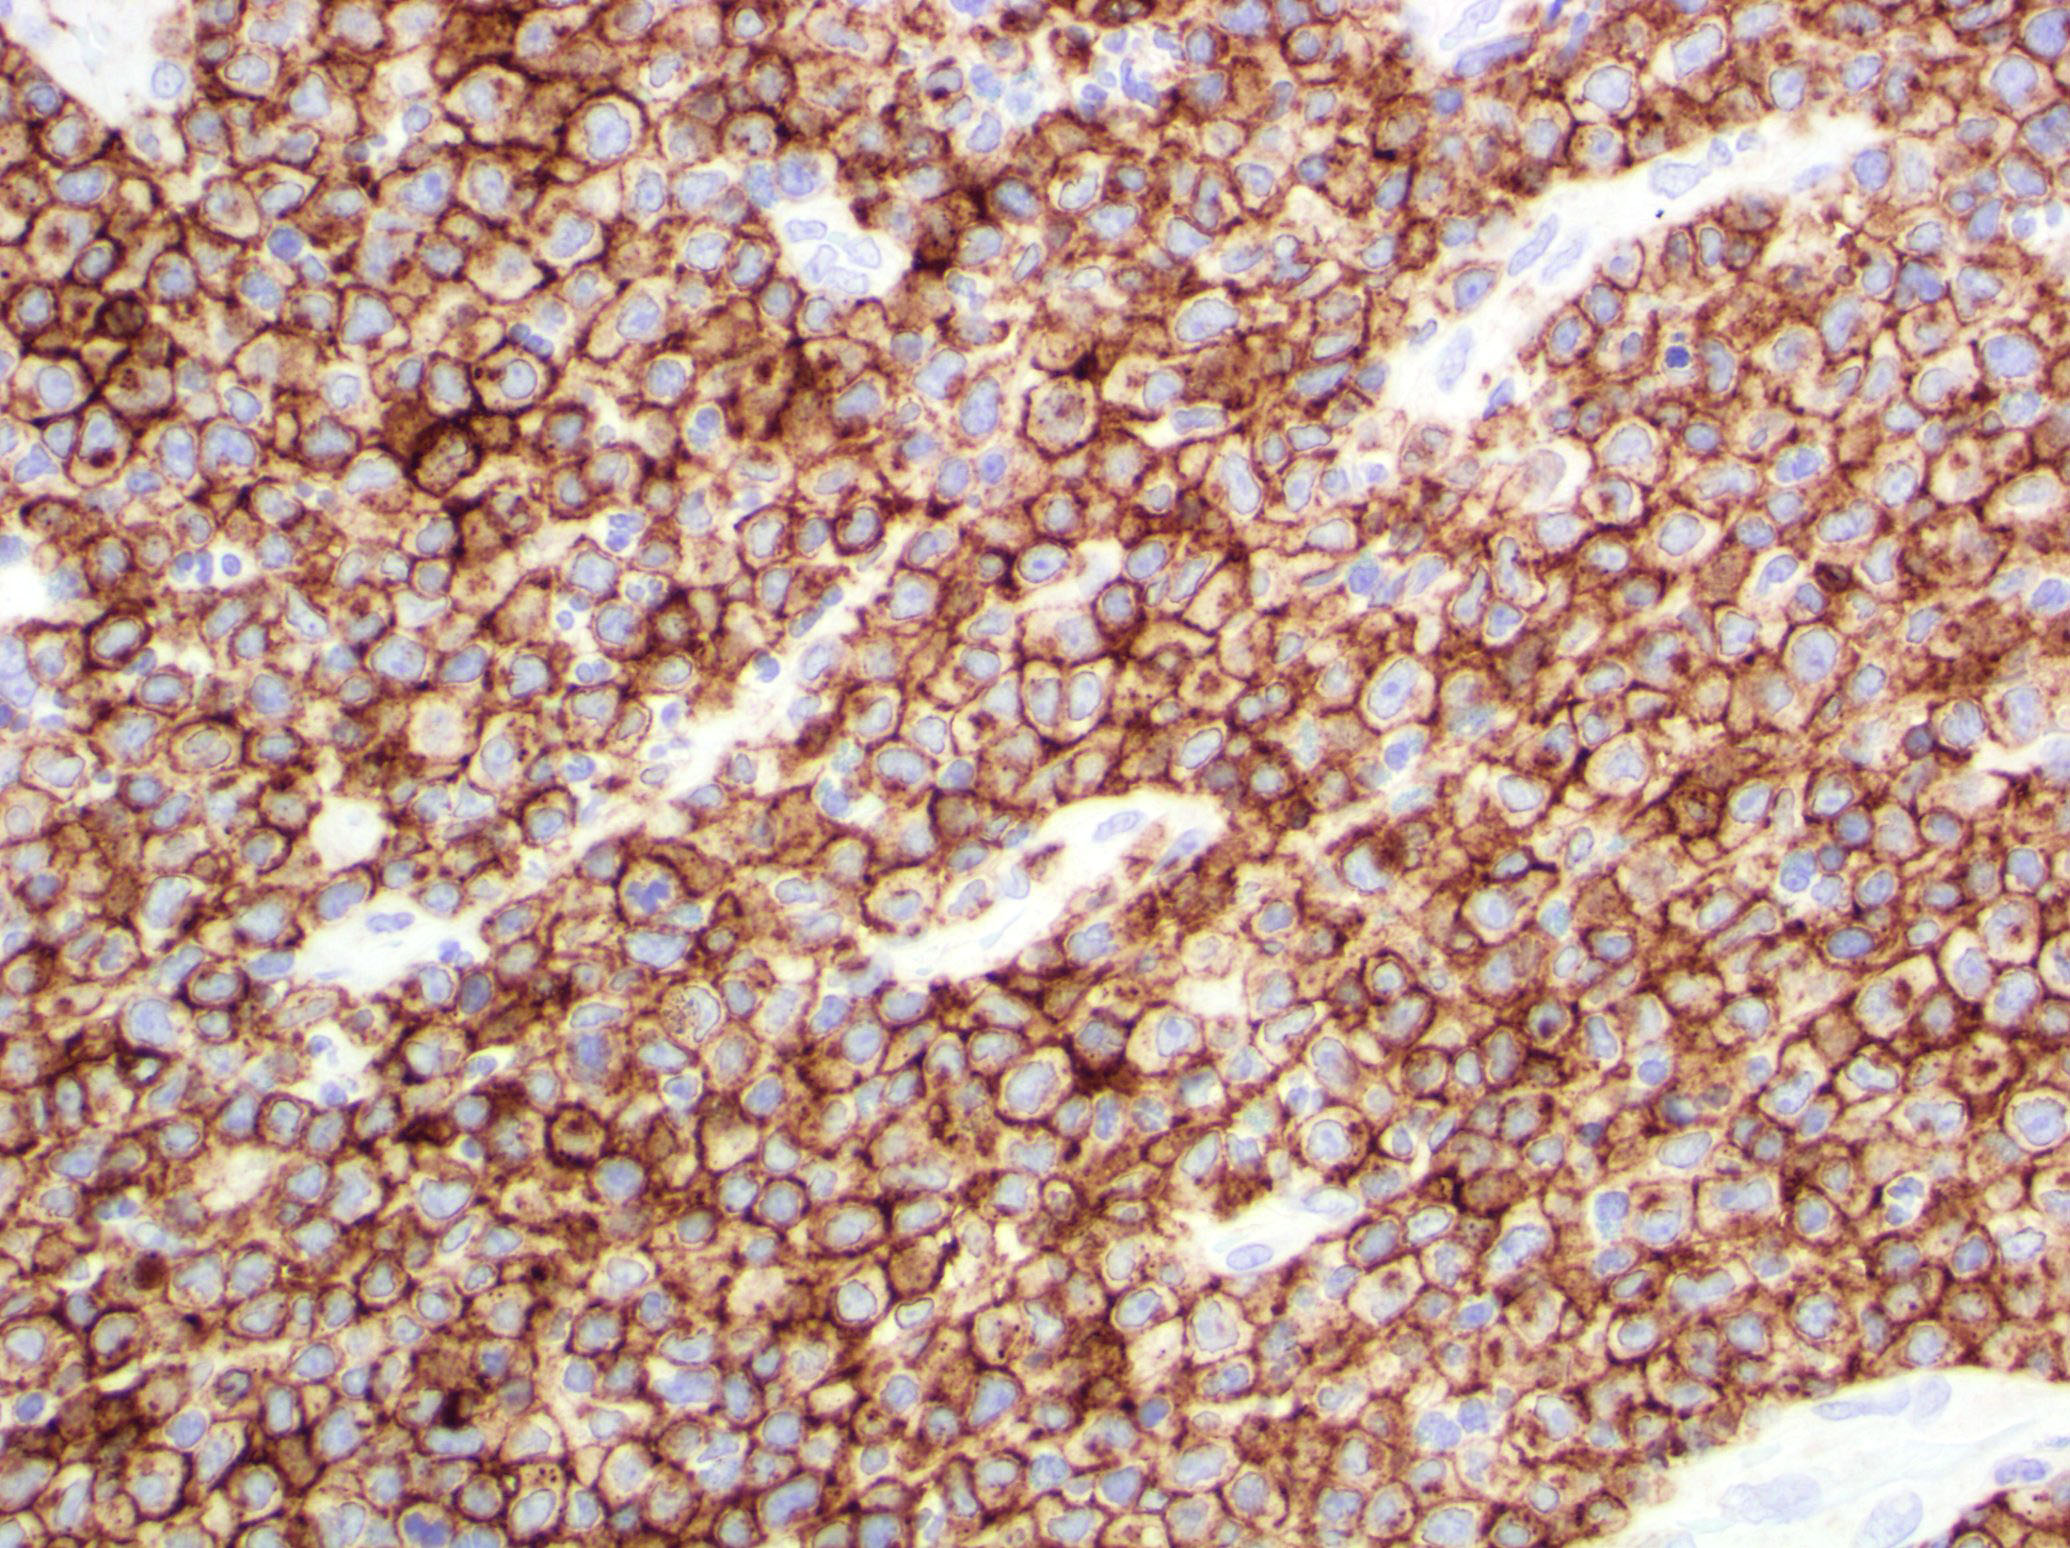

Microscopic (histologic) images

Contributed by Roberto N. Miranda, M.D.

Positive stains

- Activate T helper phenotype (Semin Diagn Pathol 2017;34:22)

Negative stains

- Usually CD8 negative (Semin Diagn Pathol 2017;34:22)

- Variable loss of pan T cell antigens (Semin Diagn Pathol 2017;34:22)

Immunohistochemical Summary of LyP Types

*All cases are anaplastic lymphoma kinase - 1 (ALK-1) negative

| Type of LyP | Reference | CD2 | CD3 | CD4 | CD5 | CD7 | CD8 | CD30 | Other markers |

| Type A | Blood 2019;133:1703 | +/- | + | + | +/- | +/- | - | + | TIA1+ |

| Type B | Blood 2019;133:1703 | +/- | + | + | +/- | +/- | - | - | TIA1+ |

| Type C | Blood 2019;133:1703 | +/- | + | + | +/- | +/- | - | + | TIA1+ |